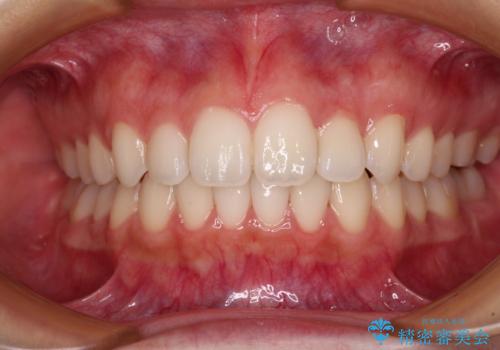

目立つ八重歯を治したい インビザラインによる矯正治療

前歯のがたつき 深い噛み合わせを改善したい